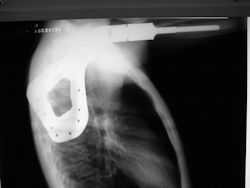

Examples of radical limb sparing surgeries for osteosarcomas in various anatomic locations (distal femur, proximal tibia, proximal humerus, scapula)

In each case, the tumor and bone from which it arose were resected. This required meticulous dissection, mobilization and preservation of adjacent pertinent neurovascular structures. In each case presented here, the defect was reconstructed with a special modular segmental tumor prosthesis. This also replaces the adjacent joint in many instances.

Proximal Humerus: Radical Limb Sparing Extra-Articular Resection and Prosethetic Reconstruction